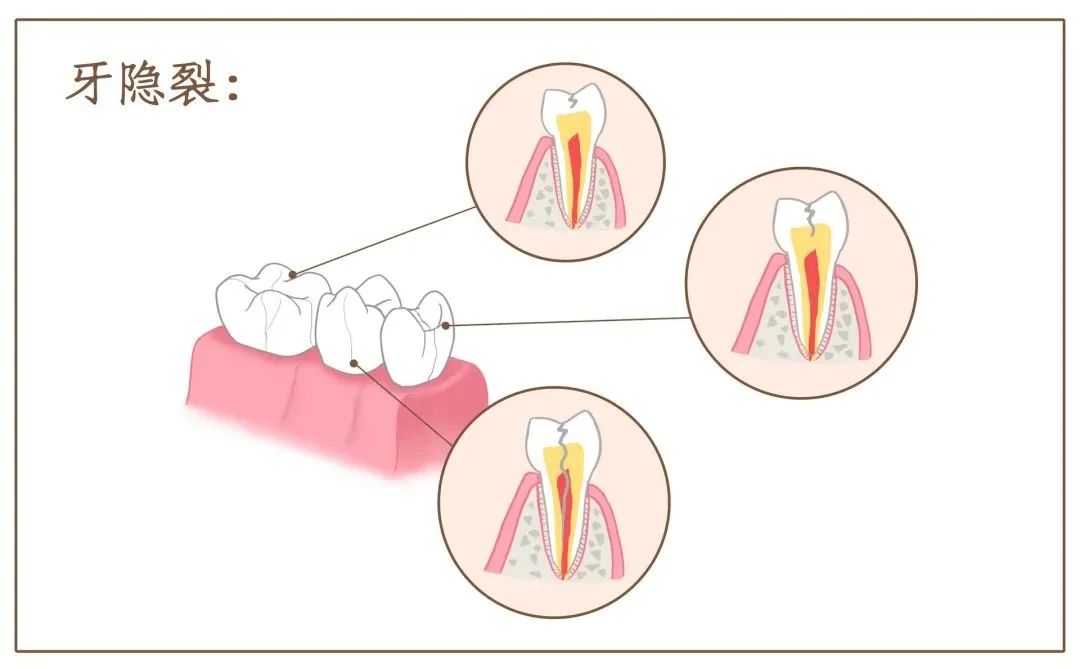

牙隐裂患者

粽子中,如有不慎包入的枣核或其他硬物,很容易硌到牙齿。牙齿有隐裂的患者要特别注意,小心误咬硬物,可能造成牙齿部分崩裂或劈裂。

所以,吃粽子时,别忘了细嚼慢咽哦~